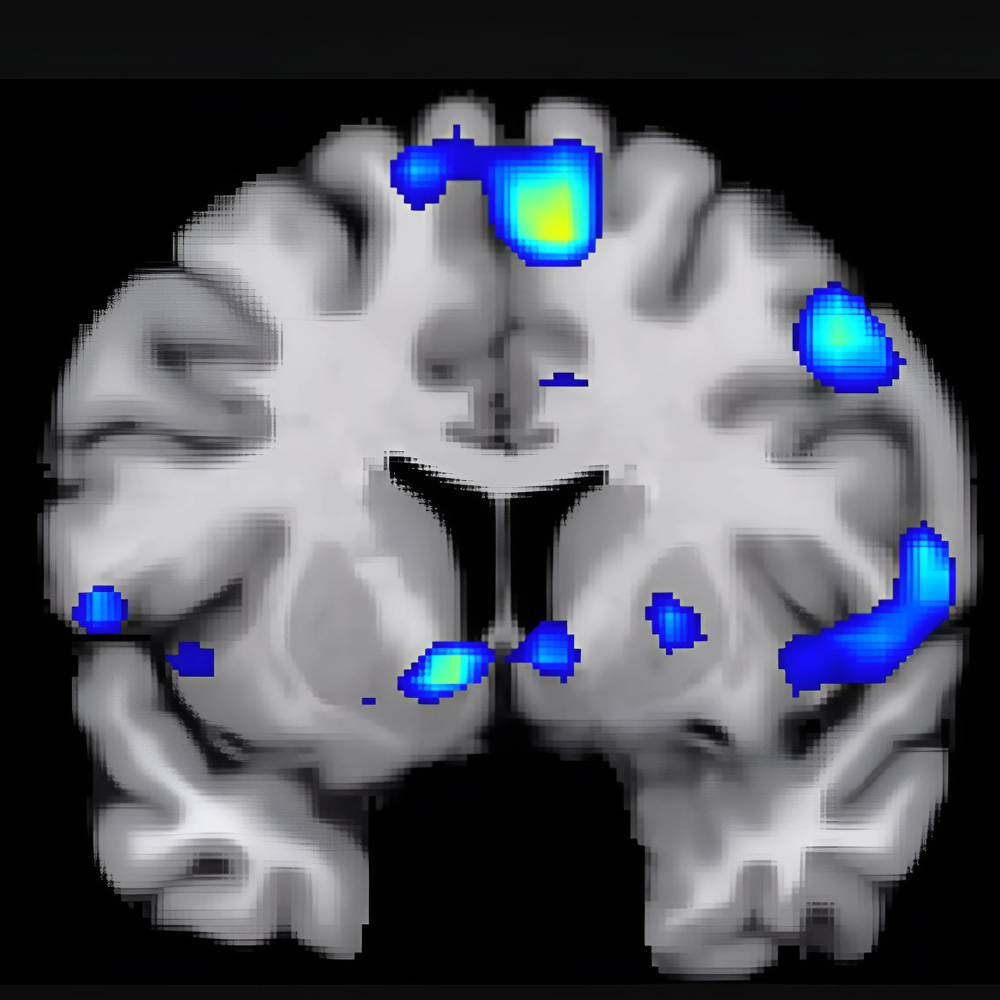

Pheromones are detected by the vomeronasal organ (VNO), a specialized receptor in the nose. Once detected, these chemical signals send messages to the brain's hypothalamus, which governs emotions, hormonal activity, and sexual behavior. This process can subtly influence feelings of attraction, trust, and even bonding.